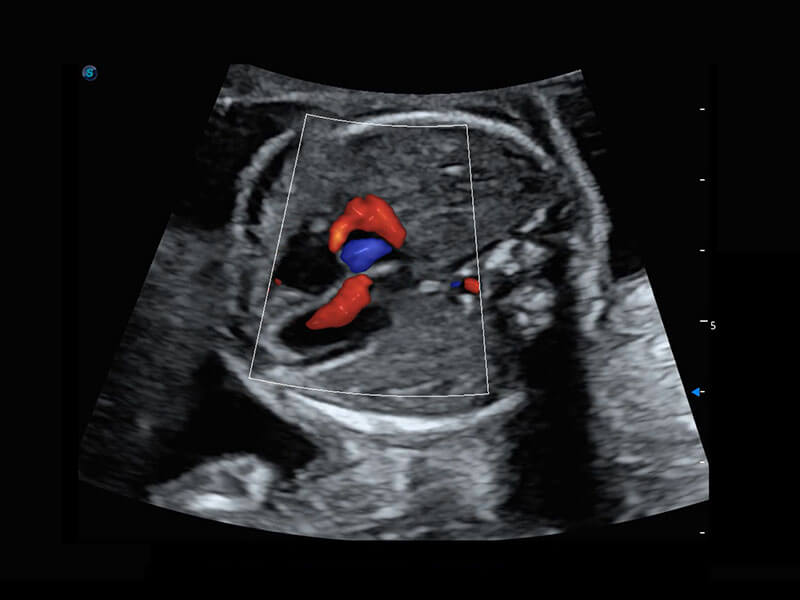

P60搭载一系列胎儿心脏成像技术,实现精细的胎儿心脏评估。

• 四腔心血流